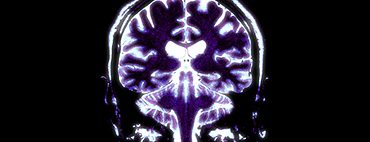

| ON THE TRAIL OF EVILIs the brain of psychopaths different or do we all have the capacity to be evil? A journey to the centre of the brain. They're charming, they lie without the slightest scruples and they are capable of manipulating their environment. Psychopaths murder and rape without regrets and can still come across as the nicest people in the world. But what is going on in their minds? more ... |